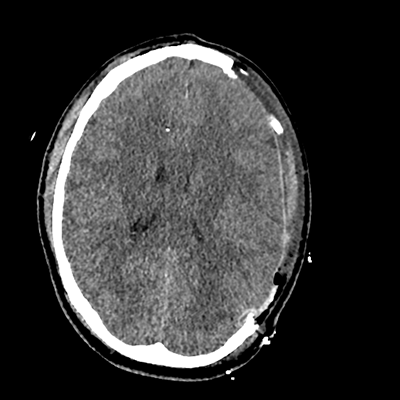

On day 5 of admission, he begins having intracranial hypertension again, spiking up to 40mmHg. You bolus with propofol and fentanyl, to no avail. You then push 30mL of 23.4% NaCl, which provides some brief improvement, allowing you to quickly get a non-contrast head CT. Unfortunately, he's now back up to 36mmHg. You review his labs, and note the following: Na 150, K 3.8, Cl 119, HCO3 18, BUN 21, Cr 0.85, glucose 136, sOsm 320.

NCHCT

NCHCT 4/20 4/20